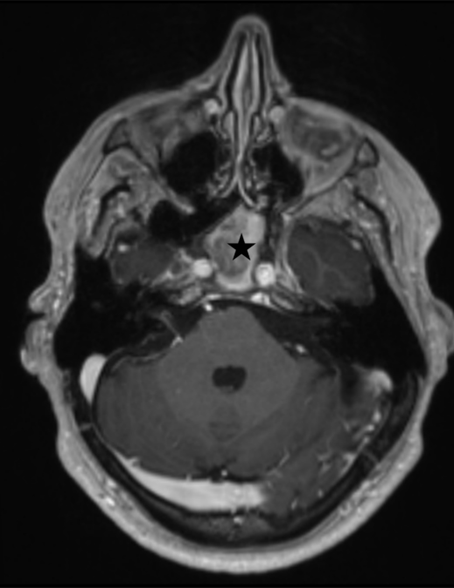

Brain MR imaging with and without contrast revealed significant sphenoid sinusitis with chronic inflammatory changes involving the adjacent clivus and areas of magnetic susceptibility raising the possibility of a superimposed fungal infection.

Figure 1. T-1 weighted axial MR image with intravenous gadolinium contrast showing the sphenoid sinus filled with high signal intensity, presumed infectious material (black star).